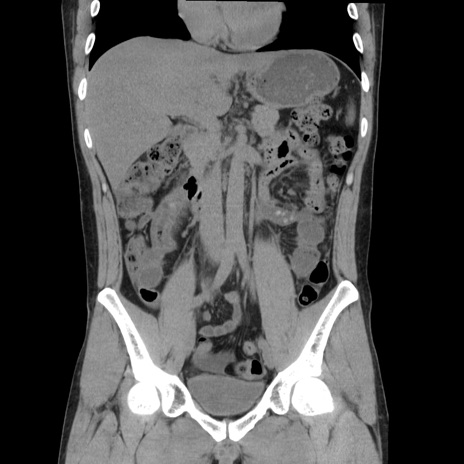

症例36(冠状断像)

【症例】20歳代 男性

【主訴】心窩部痛

【現病歴】今朝より上腹部痛あり。一旦軽快していたが再度出現したため救急要請。昨日夕に白身の魚を含む刺身を食べた。

【身体所見】BP 136/89mmHg、HR 74/min、BT 37.0℃、腹部:膨満、軟、心窩部に圧痛あり。反跳痛なし、筋性防御なし、腸雑音やや亢進あり。

【データ】WBC 17700、CRP 0.48